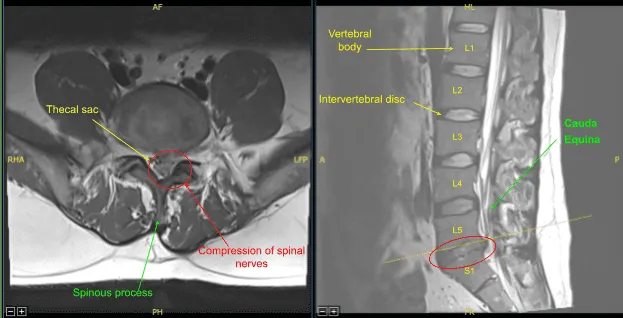

Se realizó resonancia magnética (RM), que mostró una hemilaminectomía previa izquierda en L5-S1. La hernia/extrusión del disco central izquierdo en L5-S1 contribuye al borrado del saco tecal y del receso lateral izquierdo, con estenosis y efecto de masa severa sobre las raíces nerviosas descendentes de S1 izquierda y al menos S2.